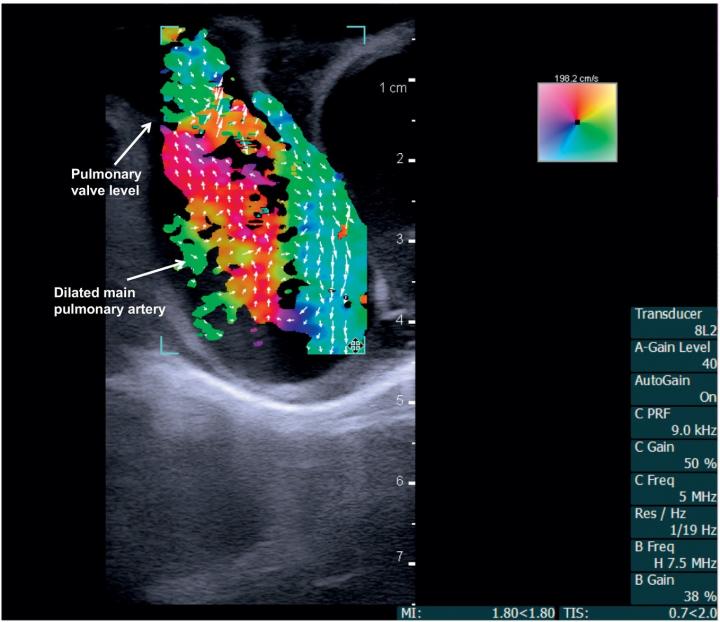

Main Pulmonary Artery

image: Vector flow imaging demonstrates swirl of blood flow within the dilated main pulmonary artery of a pig. view more

The researchers, collaborating with cardiologists at Arkansas Children's Hospital in Little Rock, tested a new ultrasound technology called vector flow imaging for the first time on pediatric patients to create detailed images of the internal structure and blood flow of the babies' hearts. The images can be still or moving, and can be taken from any angle.

Using a BK5000 Ultrasound machine with built-in vector flow imaging, the researchers performed successful tests on two pigs, one with normal cardiac anatomy and one with congenital heart disease due to a narrow pulmonary valve and a hole within the heart. The researchers then compared the vector flow images to direct examination of the pigs' hearts.

The researchers subsequently used the imaging system to take cardiac images of two three-month-old babies, one with a healthy, structurally normal heart and one with congenital heart disease because of an abnormally narrow aorta. With both patients, the technology enabled total transthoracic imaging of tissue and blood flow at a depth of 6.5 centimeters. Abnormal flow and detailed cardiac anomalies were clearly observed in the patient with congenital heart disease.